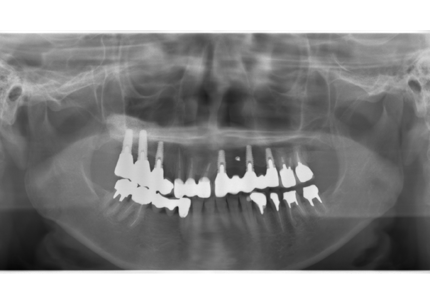

24.パノラマレントゲン

↑2006年4月24日(初診時)

↑2024年6月26日

25.初診より18年経過(2024年6月26日)